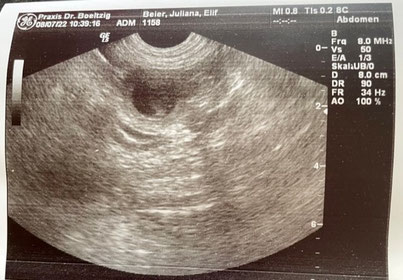

Ultraschall

Die Ultraschalluntersuchung fand am 08.07.2022 statt. Es konnten 7 mobile Welpen ausgemacht werden. Ein wenig Überraschung ist dennoch immer dabei, denn es könnten durchaus 1-2 Welpen mehr sein.